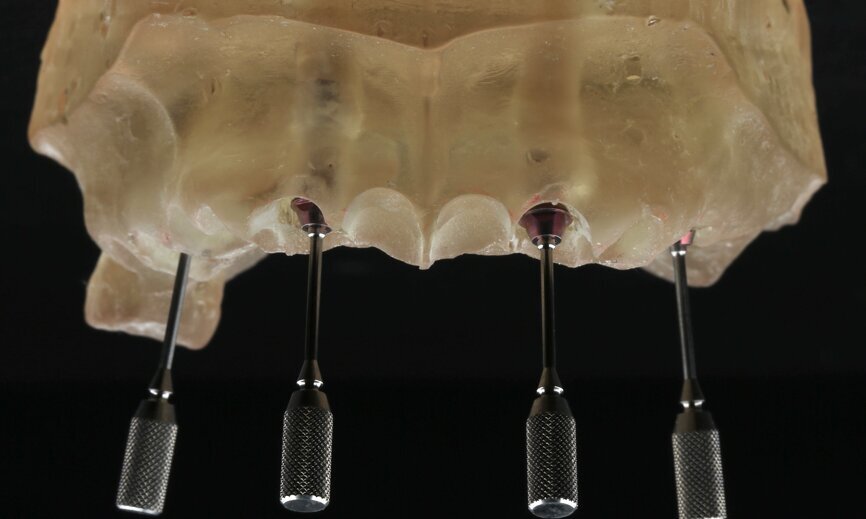

To design the prosthesis digitally, we first selected the screw-retained abutment (SRA) angle and gingival height (Fig. 14) and then we created the patient model on which we could connect the BLX implants with the SRAs selected from the Straumann library (Fig. 15). The implant placement guide was on the model, leveraging the high stability that we could gain from palatal support (Figs. 16 & 17). After printing the model, the BL  implant analogues were positioned using the template for navigation. The digital planning using coDiagnostiX (Version 9.14) allowed the dental technician to identify all the necessary parameters related to implant position (Figs. 18–22). Emergence profiles were set-up on the model (Fig. 23). The model was scanned using scan bodies, and a CAD/CAM temporary restoration was designed and milled in a PMMA-based restorative material (Figs. 24–29).

On the day of surgery, we prepared for the surgical protocol provided by the implant planning software, which guided us on the drilling sequence and the use of the appropriate instruments for the implant bed preparation (Figs. 30a & b). After the fixation pins had been allocated, teeth #17, 16, 15, 13, 12, 22, 23 and 24 were atraumatically extracted and alveolectomy was performed using a bone reduction guide (Figs. 31–36). Four implants (Straumann BLX; regular base; diameter: 4.5 mm; length: 12.0 mm) were placed, two straight implants in the anterior and two titled implants in the posterior. All the implants were stabilised to a torque of 50 Ncm (Figs. 37–43), and the SRAs were placed on top. The SRAs on the posterior implants had an angulation of 30° (diameter: 4.6 mm; gingival height: 3.5 mm) and on the anterior implants an angulation of 17° (diameter: 4.6 mm; gingival height: 3.5 mm; Figs. 44 & 45).